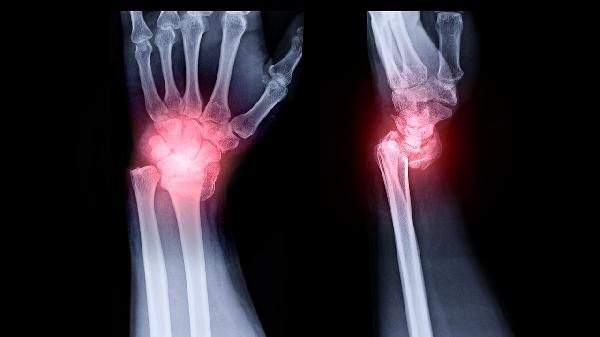

颞颌关节炎可遵医嘱使用布洛芬缓释胶囊、双氯芬酸钠缓释片、硫酸氨基葡萄糖胶囊、盐酸乙哌立松片、塞来昔布胶囊等药物。颞颌关节炎可能与关节损伤、咬合异常、免疫因素、感染或精神紧张等因素有关,通常表现为关节区疼痛、张口受限、弹响等症状。